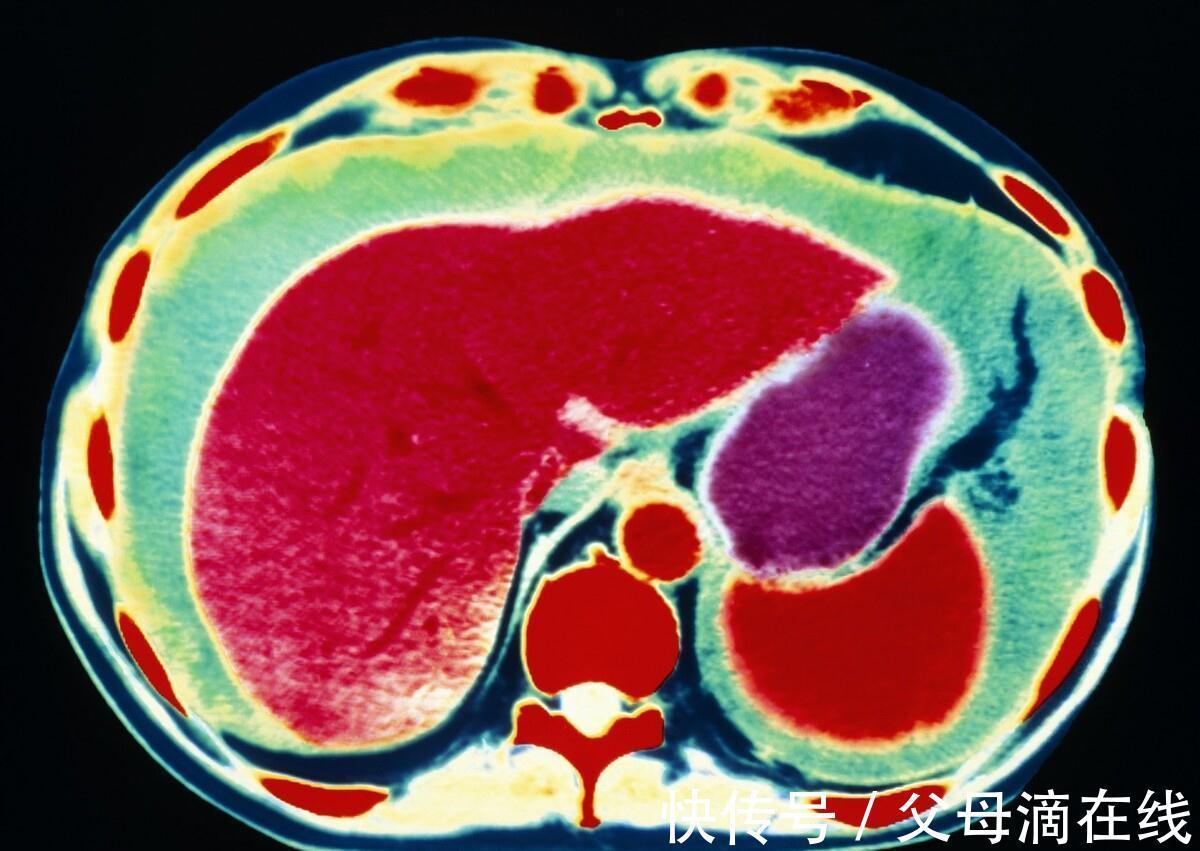

文章插图

图上显示的绿色区域就是腹腔积液